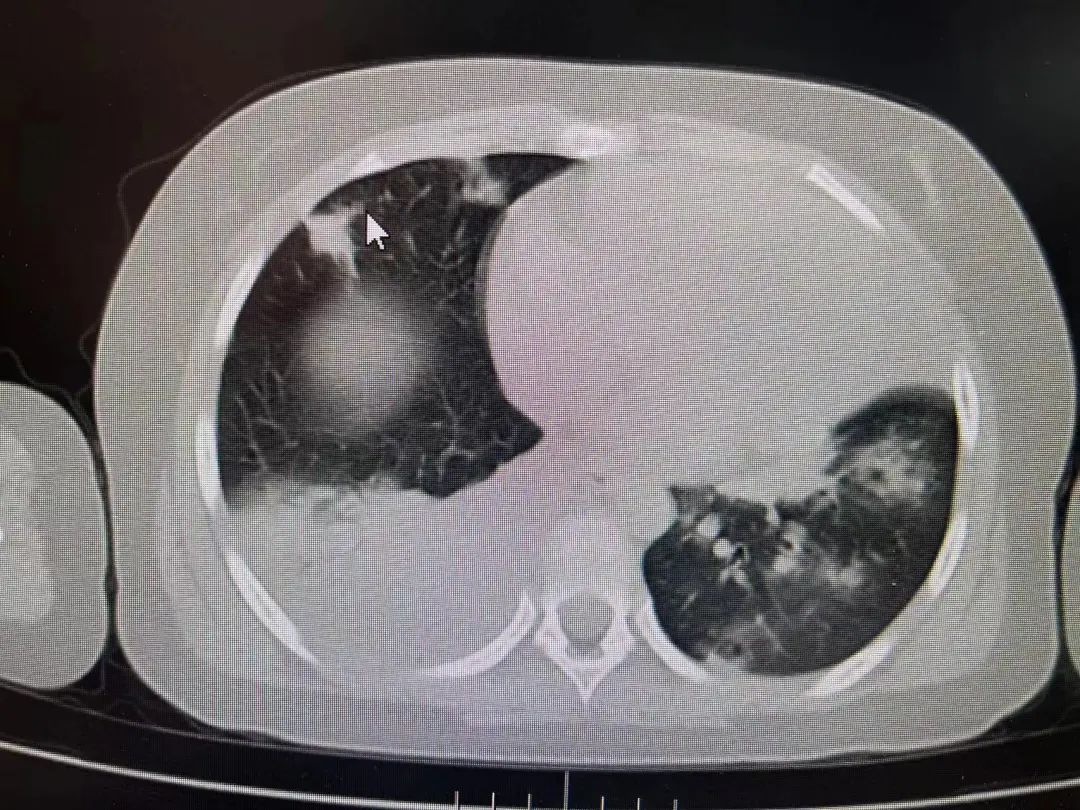

经胸部CT检查,发现患儿双肺都出现了肺不张的情况,超过2/3肺叶实变,再综合血检结果,诊断为重症支原体肺炎,遂住院治疗。在PICU治疗期间,又对症进行了支气管镜灌洗治疗,效果明显。